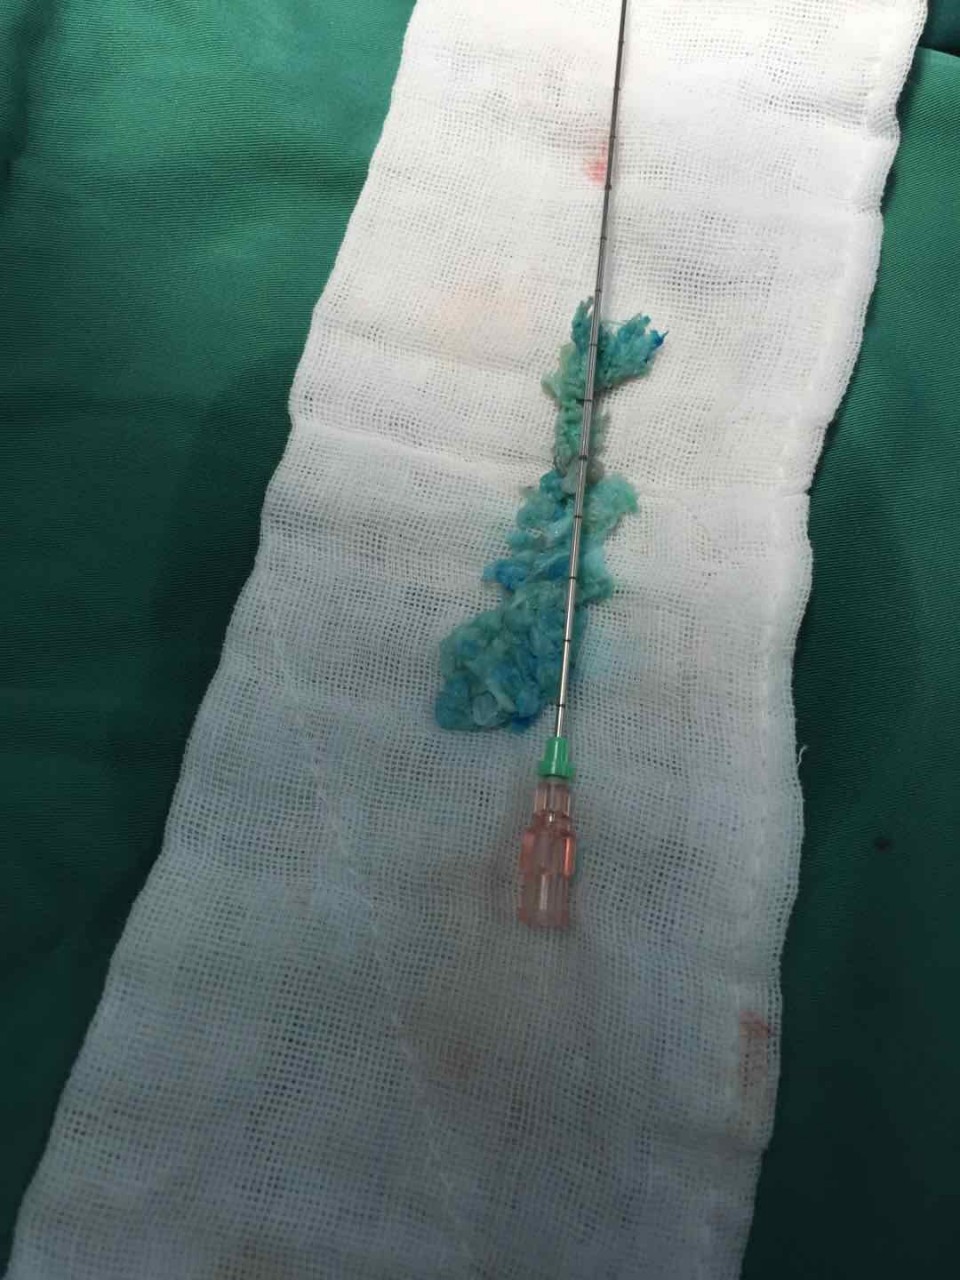

取出的巨大染色突出的椎间盘

家住合肥的患者陈某今年60岁,5月初,陈某搬重物后突然出现腰及右下肢疼痛剧烈不能行走,活动后加重。曾接受保守治疗暂时控制住病情,也自己用膏药敷贴缓解疼痛, 但效果不佳。陈某遂赴省城多家医院就诊,MRI示椎间盘膨出。腰椎退变。药物及康复治疗两天后症状加重。5月10日,陈某及家人随即来到安医大一附院疼痛科就诊。经精确诊断后确诊为极外侧型巨大椎间盘突出。这是非常少见的一种椎间盘突出类型,存在30%的误诊率。入院后陈某对传统腰椎间盘手术抱有极大的恐惧心理。一是担心手术疼痛,二是担心会造成神经损伤之类的并发症。疼痛科副主任医师宋阳通过和陈某对椎间孔镜手术详细介绍后,陈某同意手术。术前给患者做了椎间盘造影,更加准确定位突出位置和节段。术中局部麻醉完善,整个手术患者没有任何不适感觉。且可以清醒的和手术医生交流手术的疑惑。术中医生通过高清显像系统向陈某实时解释了手术目的及效果体现。在清醒舒适的状态下医患共同参与了手术过程,取出巨大椎间盘突出近7cm。如此巨大的极外侧型椎间盘突出实属罕见。

术后,陈某一天后即可下床活动,三天出院。快速康复。整个医疗过程体现出现代疼痛微创技术的三大优势:1. 精准医疗。从术前诊断到术前造影定位到术中靶向放置工作套管到术中精确减压。2.舒适化医疗。整个过程基本无痛。3. 微创化医疗。除去突出物摘除,不破环正常骨质,韧带,脂肪组织。